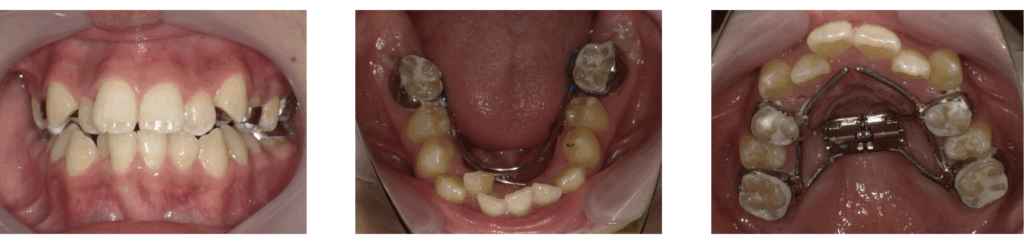

当院で急速拡大装置を使用して顎顔面矯正を行った症例をご紹介します。

症例1:急速拡大装置とブラケット装置を併用した矯正治療

| 年齢 | 8歳 |

| 性別 | 女子 |

| 治療の理由(主訴) | 前歯がねじれていて、すきっ歯が気になる。 見た目をきれいにしたい。 |

| 治療方法 | 顎顔面矯正+ワイヤー矯正 |

| 治療期間 | 1年10か月 |

| 費用 | 66万円 |

顎顔面矯正

ワイヤー矯正